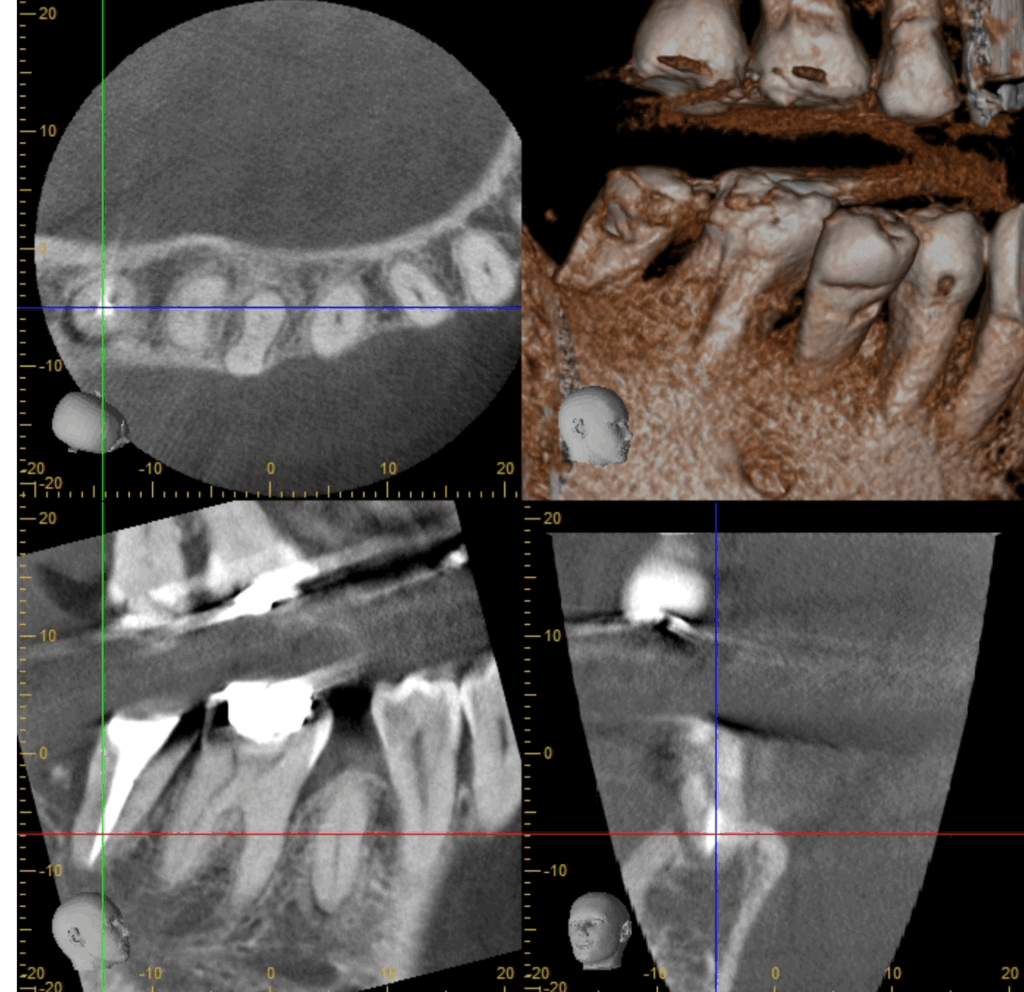

- 歯科用CT:三次元で骨や根管の形態を正確に把握

結果としてレントゲンでは「黒い影」として映し出されます。

👉 臨床的には、3~6か月で黒い影が縮小し、1年前後で完全に骨が回復するケースも多くあります。

「歯茎から膿が出続けていましたが、治療後は腫れが消え、CTで骨の再生が確認できました。」